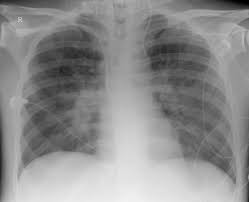

Röntgen in der stillzeit. Röntgenstrahlen haben keine Auswirkungen auf das Stillen. Röntgenstrahlen haben keine Auswirkungen auf das Stillen. Hallo Hier kann ich Sie beruhigen.

Diese wirken nur für den Moment auf dich ein in dem die Aufnahme gemacht wird. In der Stillzeit gelangen Medikamente die verabreicht oder eingenommen werden in den Blutkreislauf der Mutter. Unmittelbar danach ist die Strahlung wieder weg.

Vincenzo Bluni am 03092009. Die Mutter kann unmittelbar anschließend gefahrlos stillen. Ähnliche Fragen zum Thema Schwangerschaft und Geburt.

Beiden Trimenone appliziert werden. Hallo zusammen Ich habe da mal eine Farge meine Tochter ist 10 Monate alt und seit der Entbindung von Ihr habe ich Probleme mit meiner Hüfte rechter Hüftknochen tut weh es wird immer schlimmer jetzt sagte der Arzt es könnte eine Reizung sein aber das halte ich für mehr als ausgeschlossen 10 monate lange reizung habe reizstrom bekommen hat null geholfen. Muttermilch wird durch eine Röntgenuntersuchung nicht beeinträchtigt.

Röntgen ist während der Stillzeit immer möglich. In der Stillzeit gilt es als Analgetikum der Wahl. Röntgen ist während der Stillzeit immer möglich.

Du könntest also sogar ohne Stillpause weiterstillen wenn dir direkt die Brüste geröntgt werden würden. Röntgen in der Stillzeit.

Muttermilch wird durch eine Röntgenuntersuchung nicht beeinträchtigt.

Röntgenstrahlen haben keine Auswirkungen auf das Stillen. Das aktuelle Protokoll listet die häufigsten Untersuchungsverfahren auf die keine Unterbrechung der Stillzeit erfordern. Dieses hat keine negativen Auswirkungen. Die Mutter kann unmittelbar anschließend gefahrlos stillen. Röntgenstrahlen am Arbeitsplatz verändern die Muttermilch nicht und können sich dort auch nicht anreichern. Diclofenac hemmt reversibel und dosisab-hängig die Prostaglandinsynthese und die Plättchenaggregation. Jetzt wollte er eine Röntgenaufnahme von der Wirbelsäule machen lassen. Röntgen ist während der Stillzeit immer möglich. Unmittelbar danach ist die Strahlung wieder weg.

Eine Schädigung durch Röntgenstrahlung in dieser Zeit kann daher schlimme Folgen wie Fehlbildungen des Körpers mit sich. Muttermilch wird durch eine Röntgenuntersuchung nicht beeinträchtigt. Insbesondere in den ersten Wochen der Schwangerschaft wächst das Kind sehr schnell und alle wichtigen Organe und Körperteile werden ausgebildet. Du könntest also sogar ohne Stillpause weiterstillen wenn dir direkt die Brüste geröntgt werden würden. Ultraschalluntersuchungen Kontrastfreie Röntgenaufnahmen CT mit jodiertem intravenösem Kontrastmittel weniger als 1 der verabreichten mütterlichen Dosis kann in der Muttermilch nachgewiesen werden. Arzneiverordnung in Schwangerschaft und Stillzeit 7. In der Stillzeit gelangen Medikamente die verabreicht oder eingenommen werden in den Blutkreislauf der Mutter.